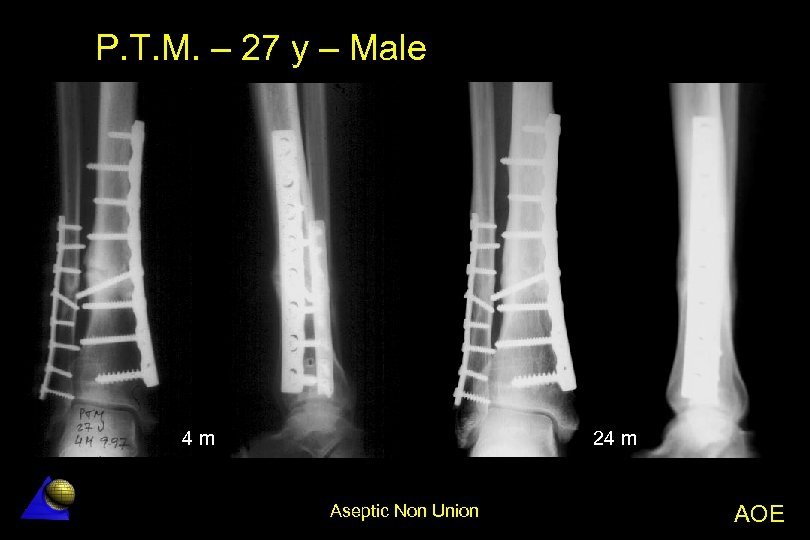

P. T. M. – 27 year old – Male Distal de tibia non-union - 5. 97 l Distal de tibia fx. treated in another Hospital â UTN nailing â Technical defect (only one distal bolt) Non-union with angular deformity l Treatment l â Decortication + Osteotomy â LC-DCP tibia and fibula plate fixation l Excellent result Aseptic Non Union AOE

P. T. M. – 27 y – Male 4 m 24 m Aseptic Non Union AOE